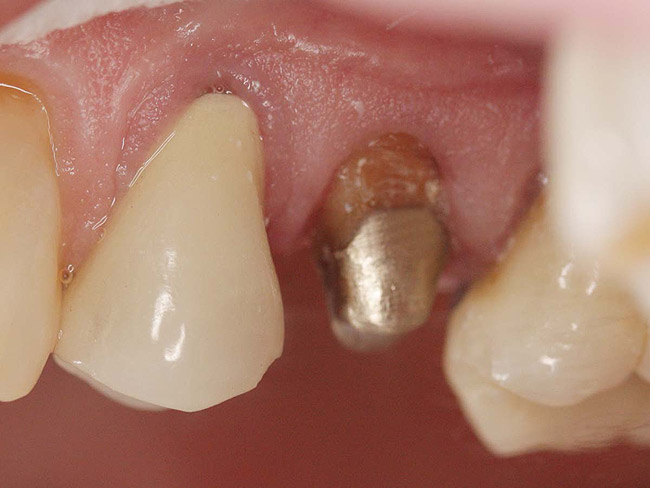

Case 1

A Class IN maxillary bicuspid was previously restored with a fiber post and an all-porcelain crown (Figure 1). The forces of the oral environment resulted in fracture of the fiber post and crown failure. The remaining fiber post in the root was removed, and anti-rotational areas were prepared for a cast post (Figure 2). A gold cast post was constructed at a dental laboratory, using an indirect technique (Figure 3). A porcelain-fused-to-metal (PFM) crown was constructed with a bevel finish to provide a ferrule and reduce forces on the post (Figure 4 and Figure 5).

Figure 3  Cast post to restore the second bicuspid.

Figure 3

Figure 4  The cast post was cemented.

Figure 4

Figure 5  The final crown.

Figure 5